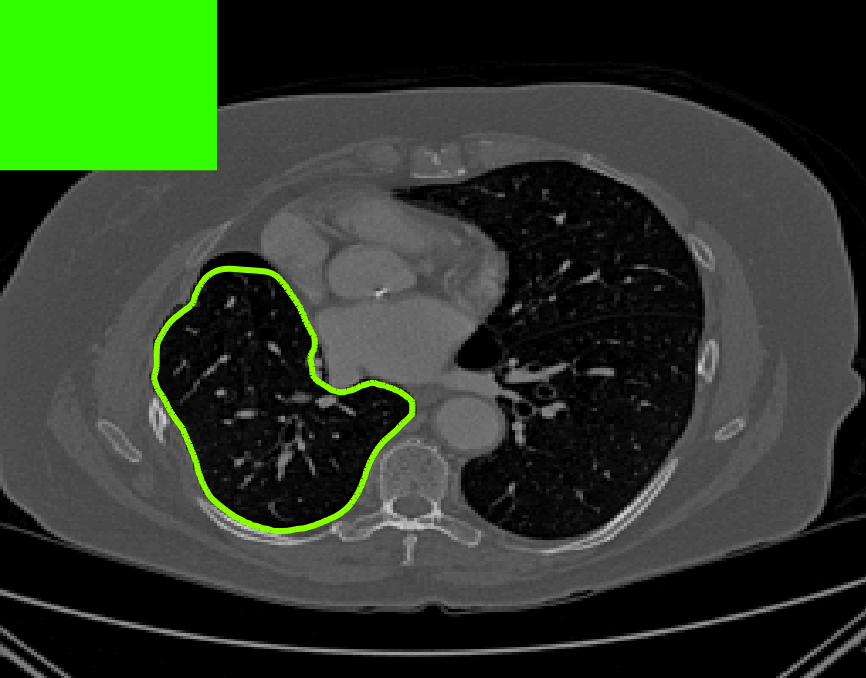

The motivation for this work comes from observing contradictions in using piecewise-constant intensity fitting terms in selective segmentation. Whilst good results are possible with this approach, the exceptional cases lead to severe limitations in practice. This is quite common in medical imaging as demonstrated in Fig. 1, where the target foreground has a low intensity. Given that the corresponding background includes large regions of low intensity, the optimal average intensities for this segmentation problem are and . For cases where , we see that by (1), almost everywhere in the domain . This means that it is very difficult to achieve an adequate result, without an over-reliance on the user input or parameter selection.

where is noise, is the characteristic function of the region , for respectively. The idea of selective segmentation is to incorporate user input to apply constraints that exclude regions classified as foreground, based on their location in the image. We use a distance constraint which penalises the distance from the user input markers. However, a key problem for selective segmentation is that for cases where the optimal intensity values and are similar, the intensity fitting term will become obsolete as the contour evolves. This is illustrated in Fig. 3. The purpose of our approach is to construct a model that is based on assumptions that are consistent with the observed image and any homogeneous target region of interest. A common approach in selective segmentation is to discriminate between objects of a similar intensity Rada:13 ; Geo ; CDSS . However, the fitting terms in previous formulations Klodt:13 ; Rada:13 ; Geo ; CDSS aren’t applicable in many cases as there are contradictions in the formulation in this context. We will address this in detail in the following section.

[\capbeside\thisfloatsetupcapbesideposition=left,top,capbesidewidth=1.5in]figure[\FBwidth]

for and as defined in (33). This is consistent with respect to the intensities of the observed object and the concept of selective segmentation. In Fig. 3 we see the difference between CV and the proposed fitting terms for given user input on a CT image. For the CT image, the CV fitting terms are near 0 within the target region. This is despite there being a distinct homogeneous area with good contrast on the boundary. This illustrates the problem we are aiming to overcome. With the proposed fitting term this phenomenon should be avoided in cases like this. By defining as in (33) there is no contradiction if the foreground and background intensities of the target region are similar.